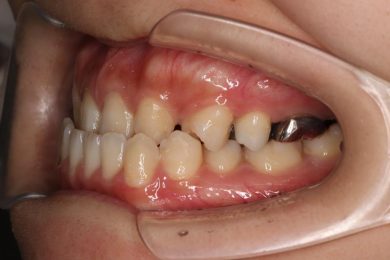

先天性欠如による上顎前歯欠損部にインビザライン術前矯正とインプラントを埋入した症例

初診時・インプラント・終了時